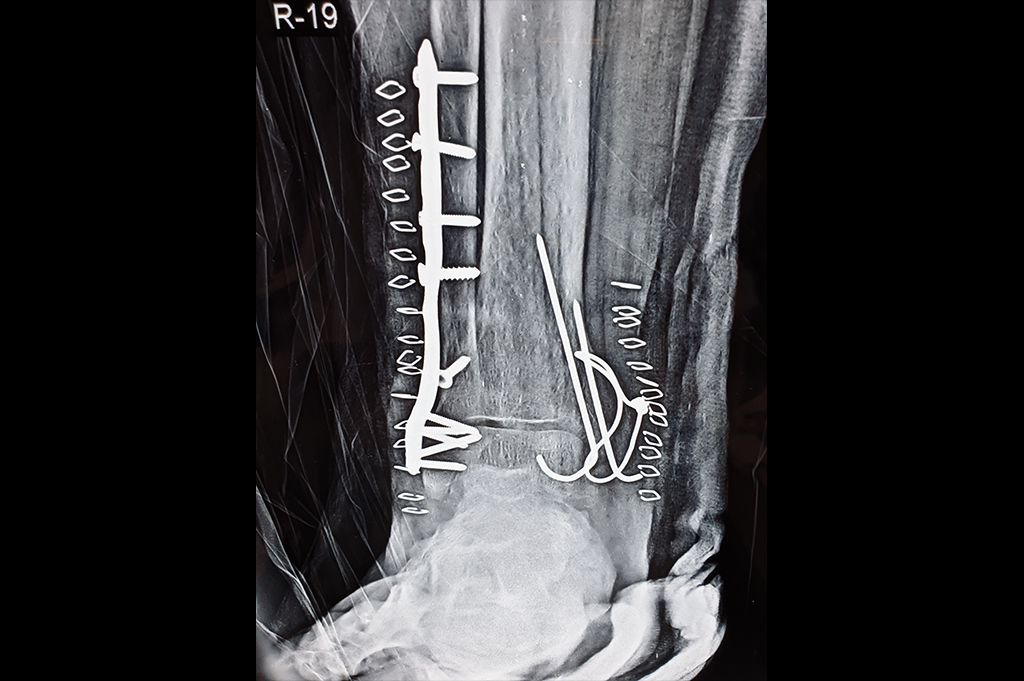

Ankle